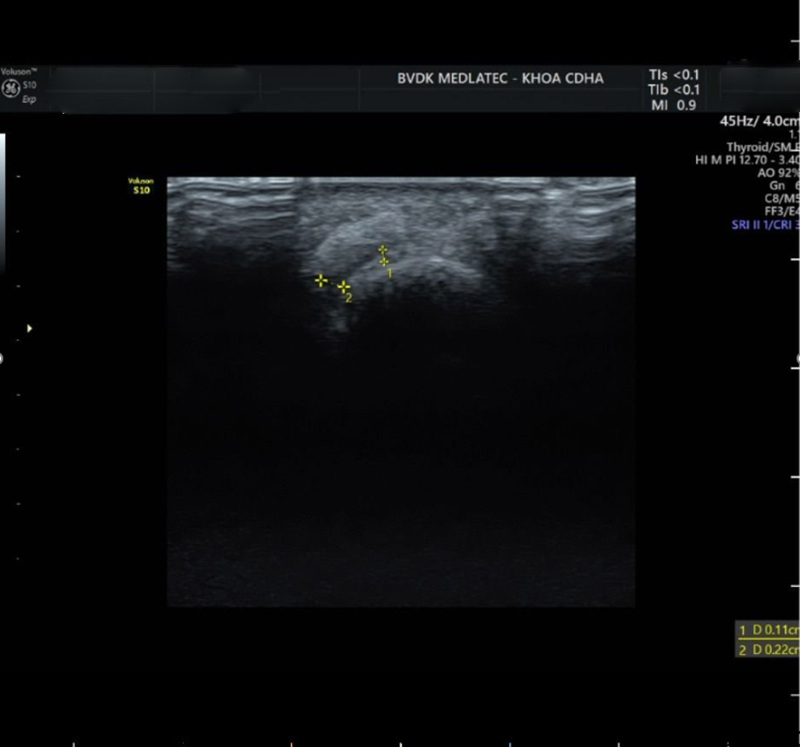

Tại bệnh viện, bác sĩ thăm khám lâm sàng thấy ngón 1 chân trái có triệu chứng sưng nóng đỏ, ấn đau, hạn chế vận động do đau. Xét nghiệm máu, chỉ số acid uric tăng rất cao (636.78 µmol/L); chỉ số men gan AST, ALT, chỉ số mỡ máu cũng đều tăng cao. Siêu âm thấy hình ảnh viêm màng hoạt dịch kèm dịch khe đốt bàn ngón 1 chân trái…

Hình ảnh siêu âm của bệnh nhân cho thấy có dịch khe đốt bàn ngón 1 chân trái